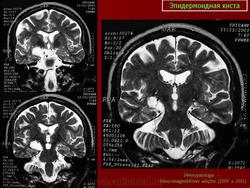

Эпидермоидная киста

Эпидермоидная киста.

Из архива AFIP